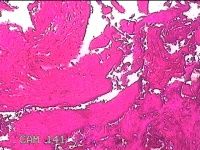

宫腔内容物

性别

女

年龄

28岁

临床诊断

不全流产?

一般病史

人流术后1月余,发现宫腔异常回声4天。

标本名称

大体所见

灰白暗红色不规则碎组织3x2.8x0.8cm一堆。